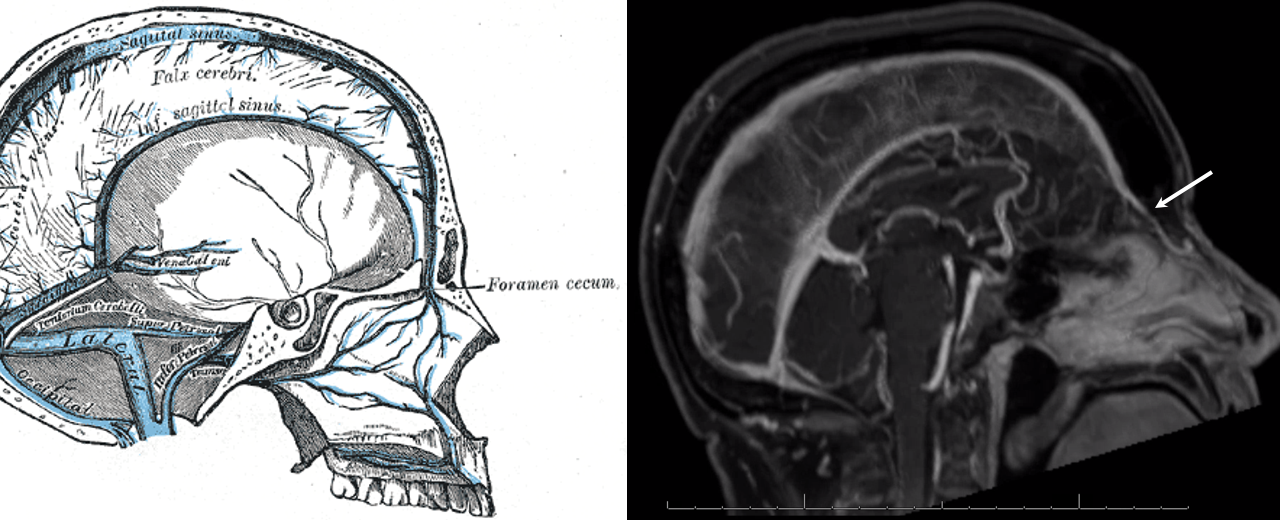

Foramen Cecum Vein and SSS hypoplasia

Case courtesy Eytan Raz, MD Ph.D.

Vein of Foramen Cecum — a rare variant of embryonic significance but i must say not too much functional significance usually. Foramen cecum transiently contains a dural tail connecting anterior cranial fossa to nasal skin during development. The foramen usually fills with cartilage or bone, but when it is patent it can contain a vein. In this patient with hypoplasia of the superior sagittal sinus there is remarkable reorganization of venous drainage, favoring cavernous sinuses, the superior ophthalmic vein, and likely also responsible for relative prominence of foramen cecum vein

Anaglyphs